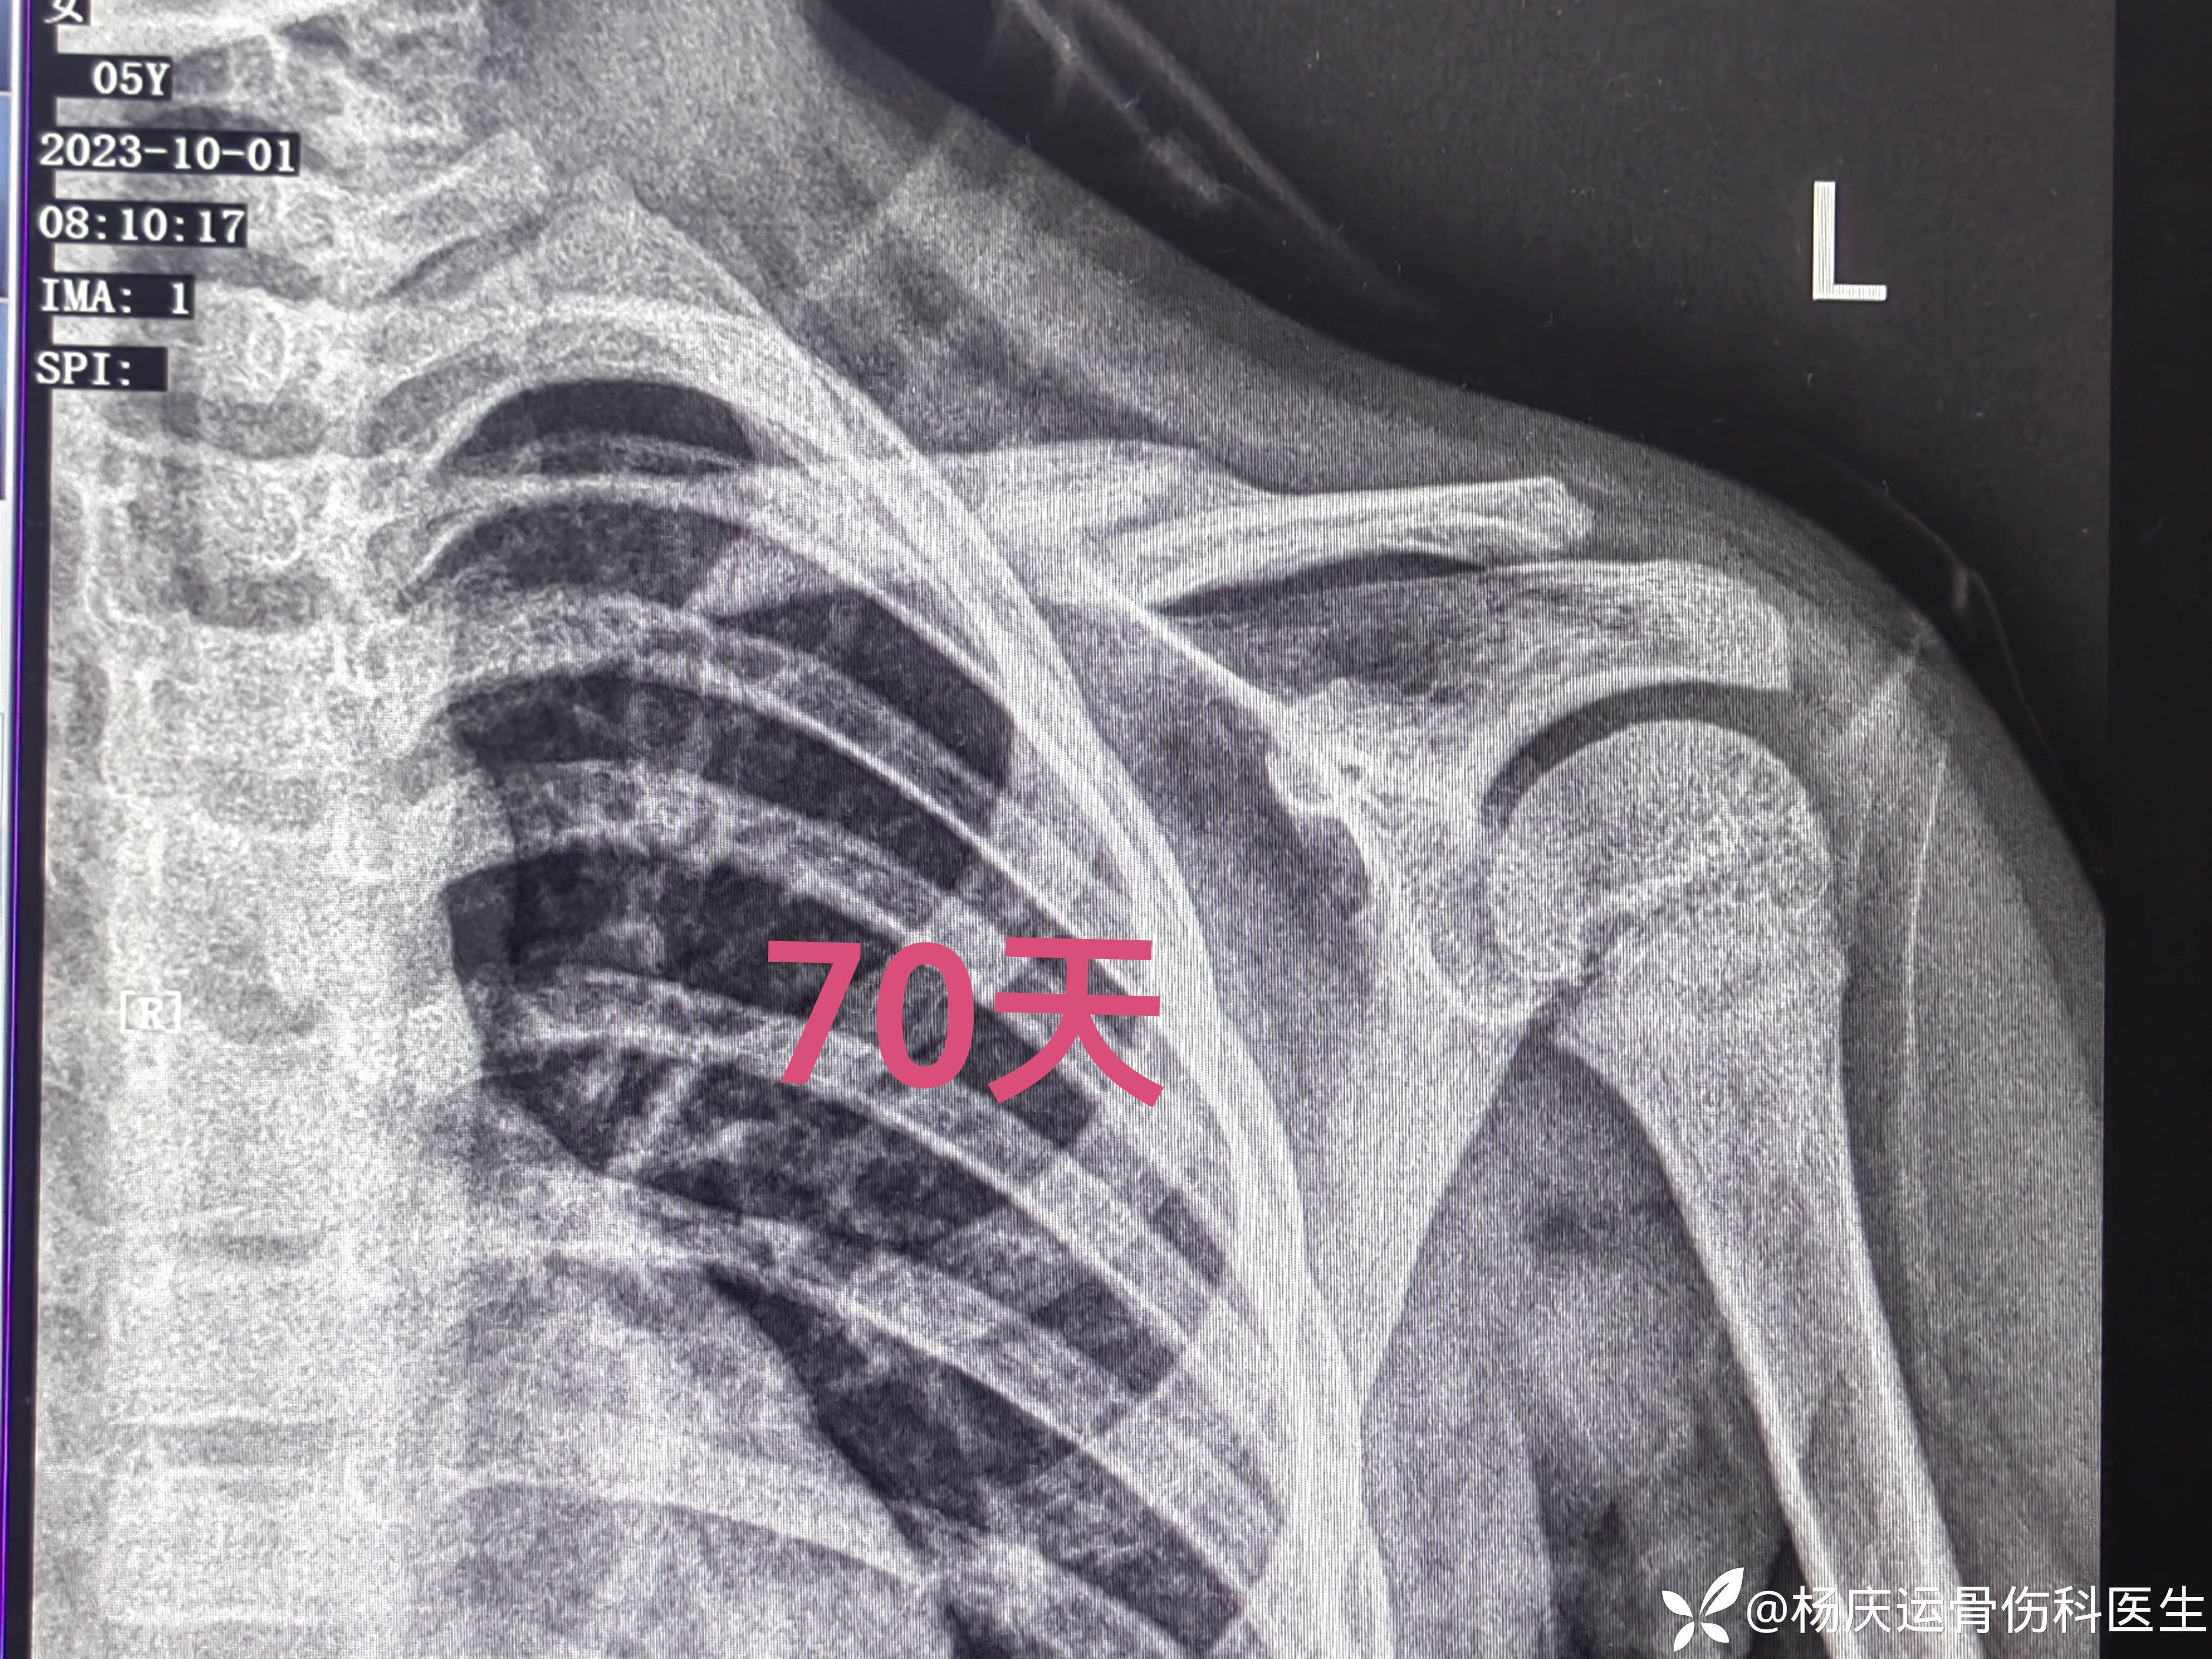

2个月余复查